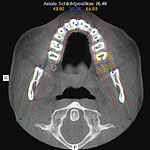

Im folgendem sehen Sie die Darstellung eines Teils des menschlichen Schädels mit Lokalisation des Nervkanales.

Orthopantomogramm (OPG) (Nervverlauf farblich dargestellt) |